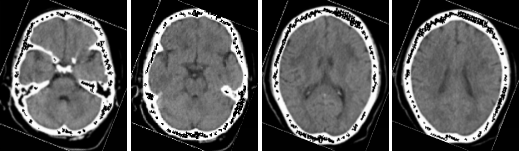

病例三 男,66歲, 突發(fā)頭痛30分鐘, 顱內(nèi)多發(fā)小動(dòng)脈瘤。

CT平掃可見(jiàn)顱內(nèi)左側(cè)小腦區(qū)有環(huán)形高密度影,CTA- MIP中顯示左小腦后下動(dòng)脈瘤, 直徑 約3 mm(黃箭頭所指)

VR圖像中清晰可見(jiàn)前交通動(dòng)脈處小動(dòng)脈瘤1直徑約2mm(紅箭頭所指)

有文章指出, 減影容積CT血管成像對(duì)于檢測(cè)腦動(dòng)脈瘤(3 - 8 mm)的敏感性: 大于8毫米為95 . 6 %左右, 而對(duì)于小于3毫米的微動(dòng)脈瘤卻很容易漏診。

640層寬體探測(cè)器CT擁有0 . 5 mm層厚的探測(cè)器單元, 對(duì)于細(xì)小的病變能夠清晰顯示,大大提高了對(duì)微動(dòng)脈瘤的檢出率。